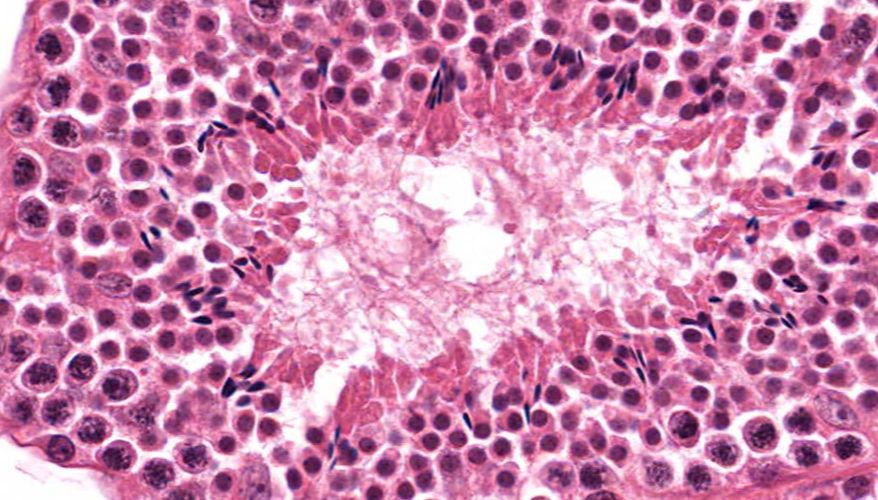

低倍镜:睾丸表面为鞘膜覆盖,其上皮为单层扁平上皮,鞘膜下是一层较厚的致密结缔组织,叫做白膜。白膜在睾丸后缘增厚,形成睾丸纵隔,其内可见不规则的腔隙,即睾丸网。睾丸内可见很多上皮性管道的切面,即生精小管的切面,呈圆形或椭圆形,管壁较厚,由生精上皮及其明显的基膜等组成。高倍镜:着重观察生精小管和其之间的睾丸间质。生精小管主要由生精上皮构成。生精上皮由生精细胞和支持细胞组成。生精细胞是一组细胞,依次自基膜向管腔面排列。

5.生精小管

6.生精上皮

8.精原细胞

9.初级精母细胞

10.精子细胞

11.精子

12.睾丸间质细胞